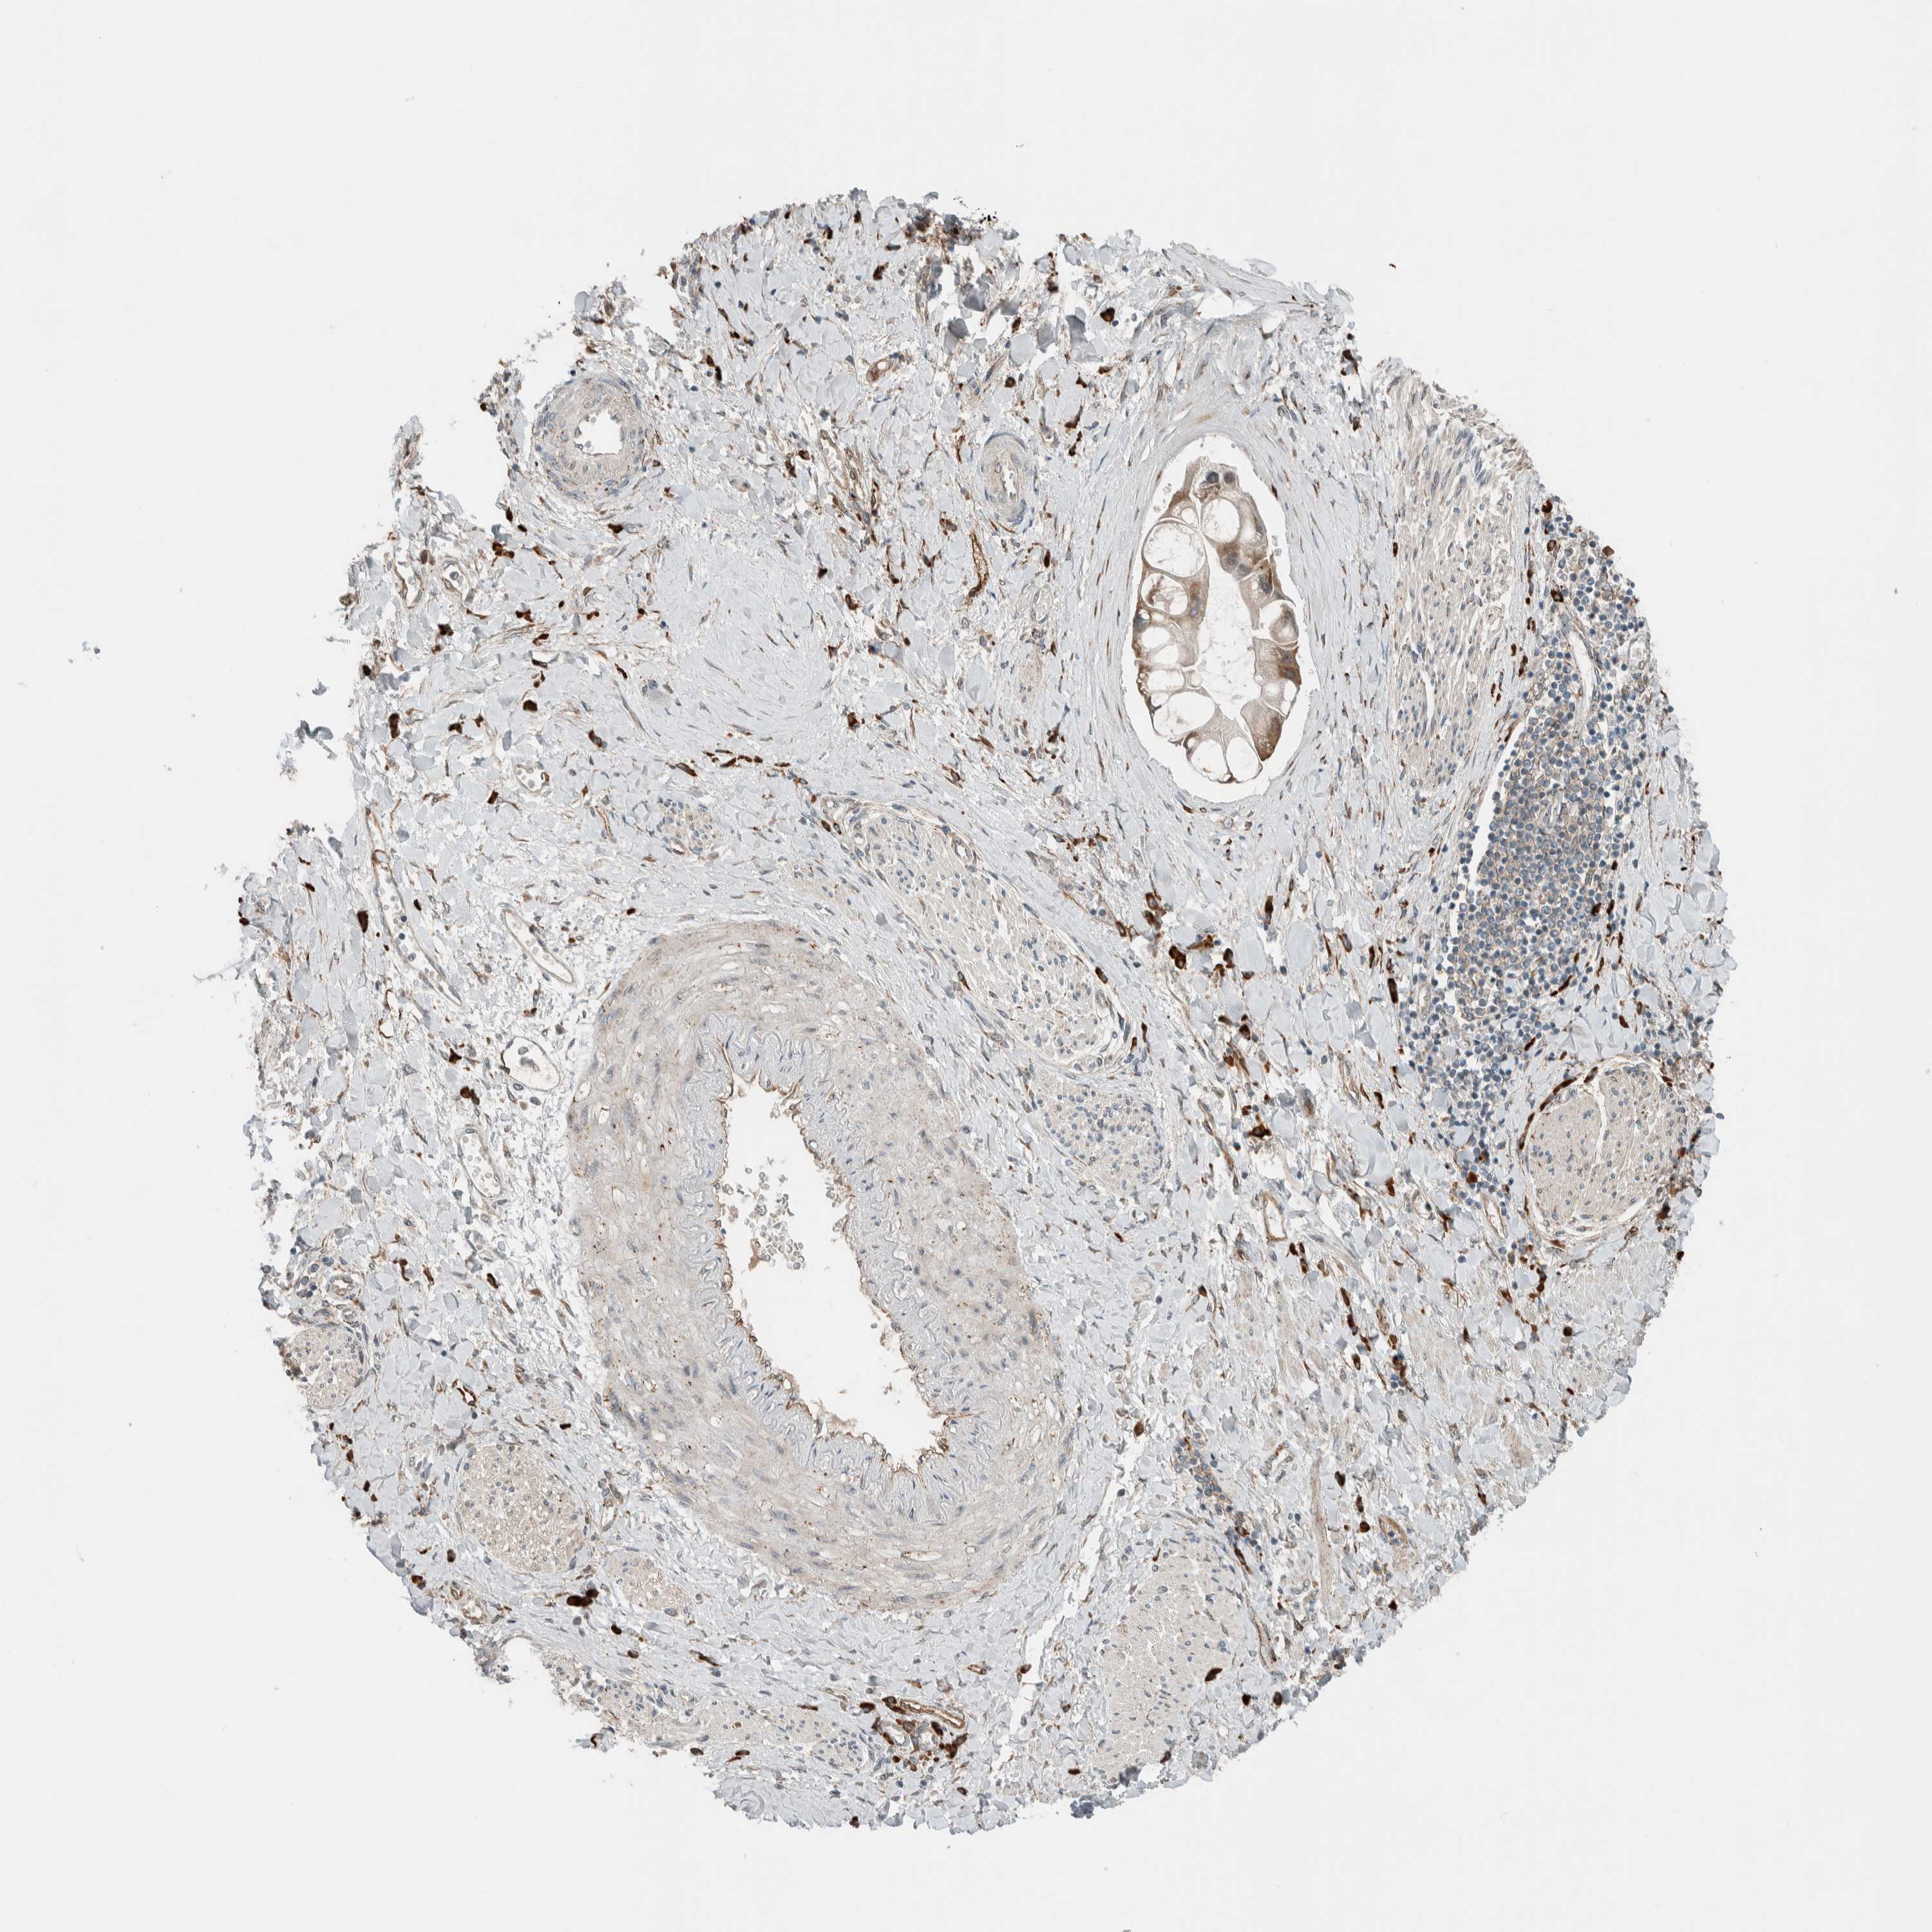

LIVER CANCER - Protein expressioni

A mouse-over function shows sample information and annotation data. Click on an image to view it in a full screen mode. Samples can be filtered based on level of antibody staining by selecting one or several of the following categories: high, medium, low and not detected. The assay and annotation is described here.

Note that samples used for immunohistochemistry by the Human Protein Atlas do not correspond to samples in the TCGA dataset.

Antibody stainingi

Antibody staining in the annotated cell types in the current human tissue is reported as not detected, low, medium, or high, based on conventional immunohistochemistry profiling in selected tissues. This score is based on the combination of the staining intensity and fraction of stained cells.

Each image is clickable and will lead to virtual microscopy that enables deeper exploration of all samples and also displays staining intensity scores, fraction scores and subcellular localization as well as patient and tissue information for each sample.

Antibody HPA023559

Antibody HPA023564

Antibody HPA044971

Antibody CAB031916

Cholangiocarcinoma

Carcinoma, Hepatocellular, NOS